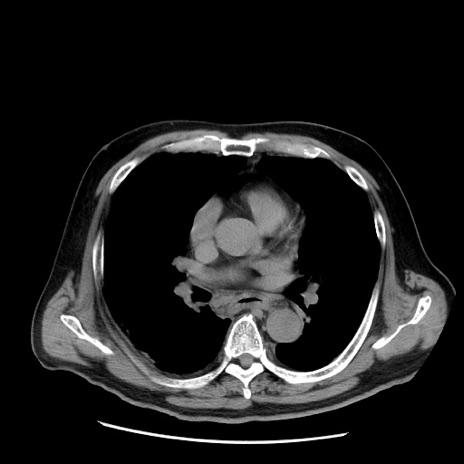

症例20(横断像)

【症例】 60歳代男性

【主訴】 腹部膨満、嘔吐

【現病歴】5日前頃より倦怠感を認め食事量減少し4日前の朝嘔吐、食事摂取困難となった。 3日前近医受診し点滴施行され整腸剤などを処方された。 当日他院を受診し、腹部膨満著明、炎症反応の上昇(CRP10.8、WBC11200)あり、紹介受診となる。

【身体所見】 意識JCS1 受け答えがはっきりしないBP 111/57mHg、 P 67bpm、、BT35.2°C、SpO2 97%(RA)、 腹部:膨隆、打診で鼓音あり、全体的に圧痛有り、腸蠕動音(-)、反跳痛ははっきりせず。

【データ】WBC 11400、CRP 14.20